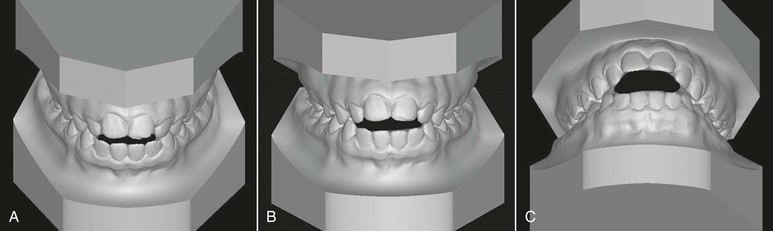

Open bite has been defined as an occlusal characteristic in which upper and lower teeth are not in contact and vertical overlap does not exist. The term was first introduced by Caravelli as early as 1842.7 Although this type of malocclusion can occur unilaterally or bilaterally in the buccal segments, it most often occurs in the anterior segment. The anterior open-bite malocclusion is most obvious when a clearance is apparent between the upper and lower incisors from the frontal view. Of course, clinical diagnosis of an anterior open bite then becomes somewhat subjective because the diagnosis depends on the horizontal plane of assessment (Fig. 9-1).

Figure 9-1 Evaluation of an anterior open bite from different planes. A, Minimal amount of anterior open bite is evident from the uppermost view angle. B, Increased open bite compared to A. Plane of assessment is almost perpendicular to the occlusal plane. C, The lowermost view angle reflects an extensive open bite, one that does not appear as extensive from the top view. The apparent magnitude of the open bite depends on the steepness of the occlusal plane and/or the plane of evaluation.